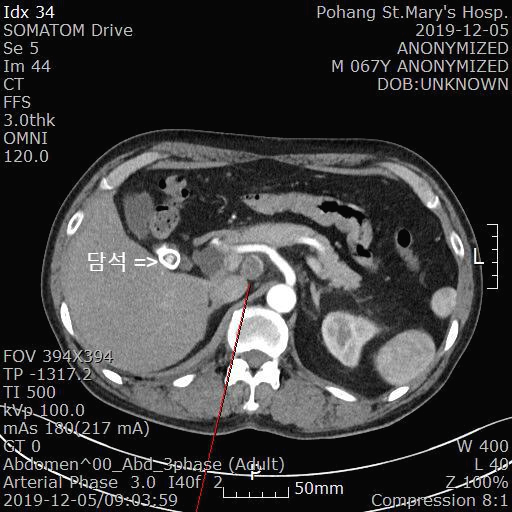

2019.12.5일 본원에서 복통으로 시행한 복부 CT 입니다.

[복부 CT 판독]

1. Multiple enlarged lymph nodes along common hepatic & splenic artery, and aortocaval & left paraaortic regions (marking on Se5)

---> R/O Metastatic lymph node (unknown origin)

---> R/O TB lymphadenopathy

2. Other findings

1) Two GB stones (max : 1.8 cm) and mild GB wall thickening ---> Chronic calculous cholecystitis, more likely

2) A 2.2 cm cystic lesion at pancreatic head portion ---> Cyst or cystic neoplasm - Recommendation : F/U after 1 yr

3) A few small hepatic cysts (1 cm or less) in segment 1 & both lobes

복강내에 여러개의 림프절이 커진 소견이 보입니다(사진에서 빨간줄로 표시됨).

첫번째로는 전이 암종(R/O Metastatic lymph node)이 의심되고 두번째로는 결핵성 림프절염(R/O TB lymphadenopathy)이 의심됩니다.

또 담낭내에 2개의 담석이 보이고 담낭벽이 두꺼워진 소견이 보입니다. 만성 담석 담낭염에 합당한 소견입니다.